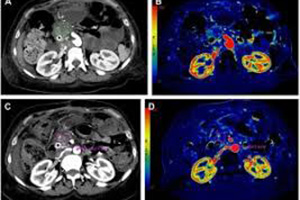

1993 Yılından bu yana İstanbul’da Tanı hizmeti veren Star-Test, teknoloji ürünü en gelişmiş radyolojik cihazlara sahip olup